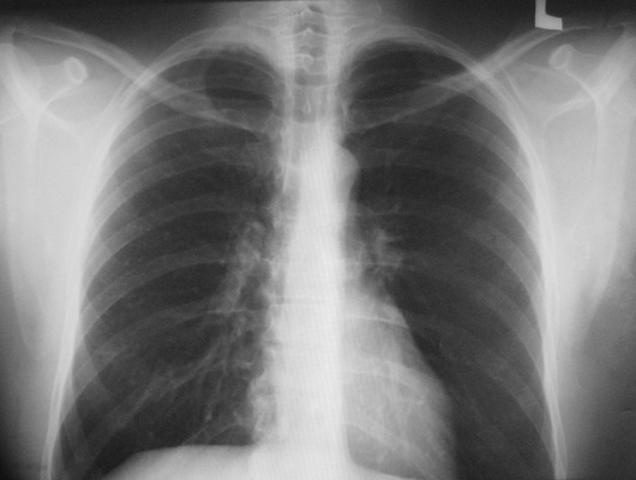

Представленный скрининговый метод помогает выявить патологии лёгких и средостения. В первую очередь флюорография грудной клетки дает понять, есть у человека туберкулез, пневмония, доброкачественные и злокачественные опухоли.